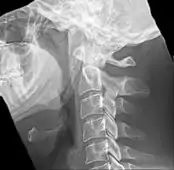

La apófisis alargada o calcificación del ligamento estilohioideo suelen mostrarse fácilmente a través de una prueba radiográfica. De forma adicional se puede realizar un TAC para confirmar el diagnóstico y ver qué estructuras están siendo afectadas.[10]